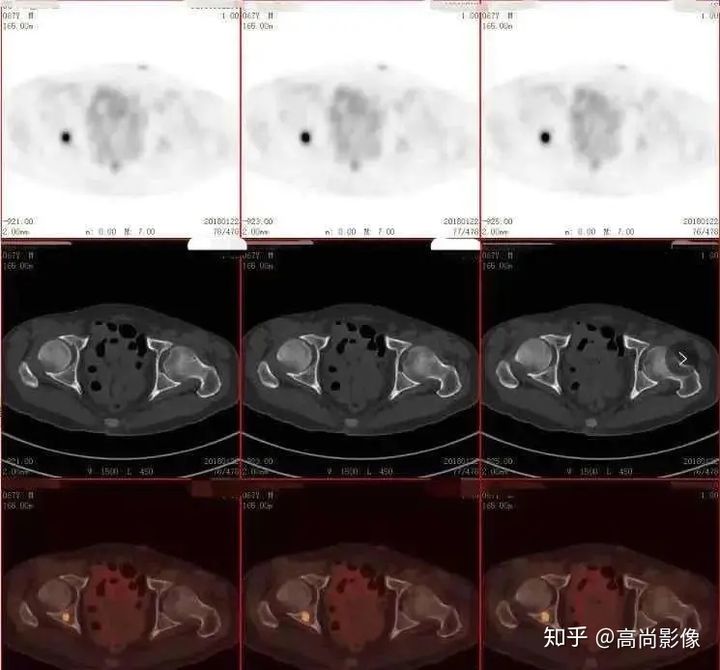

(胸椎骨轉(zhuǎn)移合并病理性骨折)

(右側(cè)髖臼骨轉(zhuǎn)移)

(右肺癌全身多發(fā)轉(zhuǎn)移)

(右肺上葉中央型肺癌)

方大爺?shù)腜ET/CT結(jié)果強烈提示肺癌伴全身多發(fā)轉(zhuǎn)移,已經(jīng)失去手術(shù)機(jī)會,但仍有繼續(xù)化療的機(jī)會。